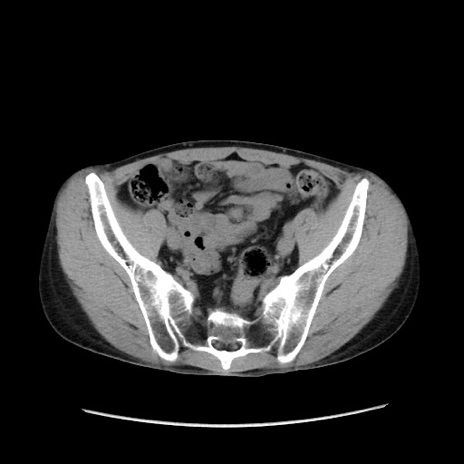

症例37(横断像)

【症例】40歳代 男性

【主訴】腹痛

【現病歴】4時間ほど前に電車に乗車中に臍部上より腹痛出現。徐々に増悪し起立困難となり、救急外来受診。生ものは数日食べていない。今朝お雑煮を食べた。

【身体所見】BT 36.8℃、BP 117/84mmHg、HR 91/min、SpO2 97%、苦悶様、腹部:臍上部広範囲圧痛あり、反跳痛±

【データ】WBC 8100、CRP 0.03